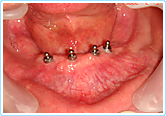

【インプラント無歯顎術前】

下顎総入れ歯が動いて 噛めませんでした

【インプラント無歯顎術後】

インプラントを4本埋入し、ボールアタッチメントを装着しました

義歯も動かなくなり 噛む力も増えました